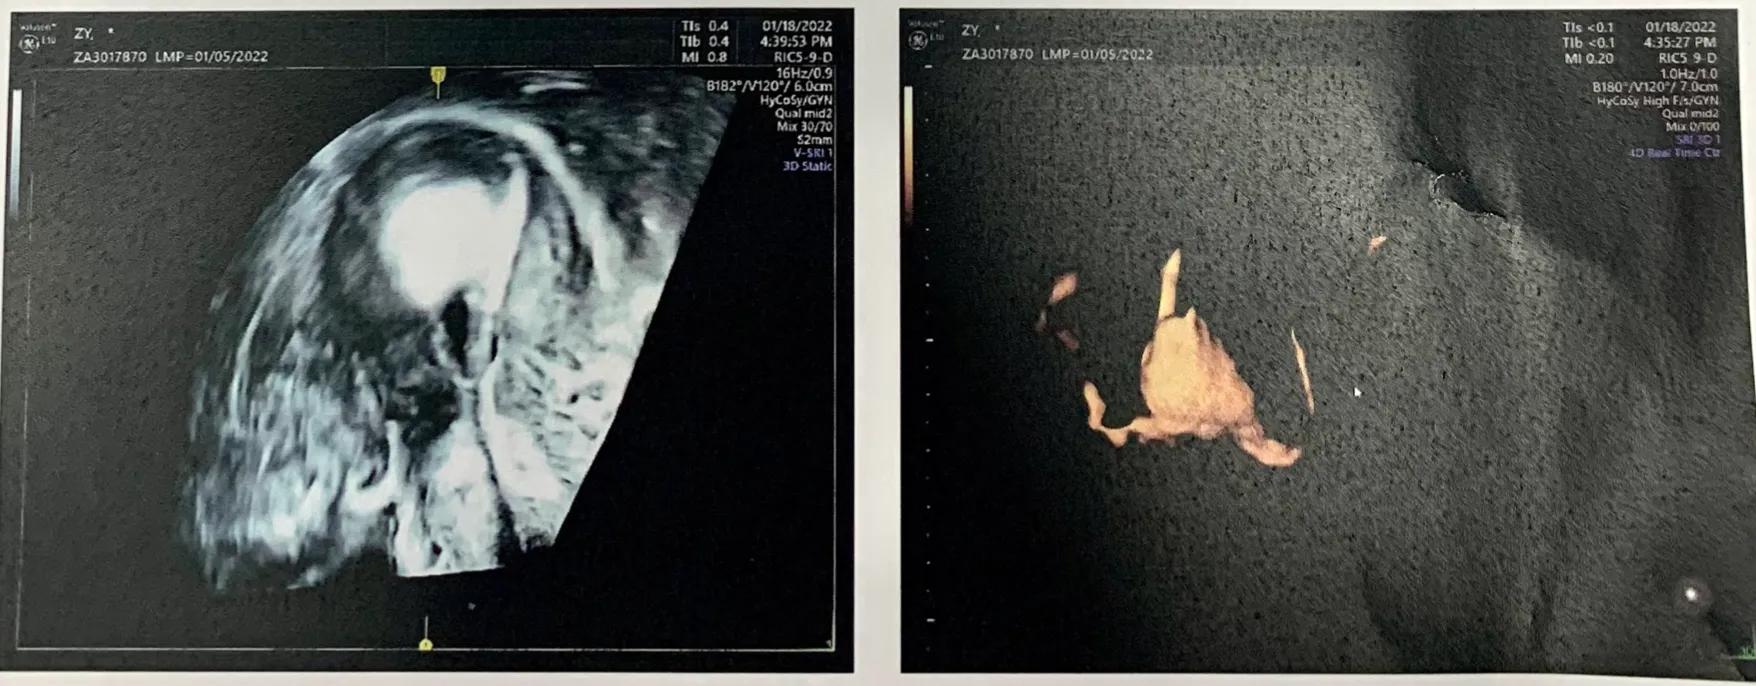

第三步,阴道四维超声造影 ,通过第一步放置的导管,将造影剂(六氟化硫微泡*干粉冻**针)推进输卵管内,这样可以通过超声探头,清楚观察输卵管情况,正常无堵塞的话,推入过程顺畅,造影剂会从宫腔内的输卵管端进入,输卵管伞端即链接卵巢的一端流出,如有堵塞,也可以清楚看到堵塞部位和严重程度,我也可以通过超声仪面向我的屏幕看到图像。

造影超声图像